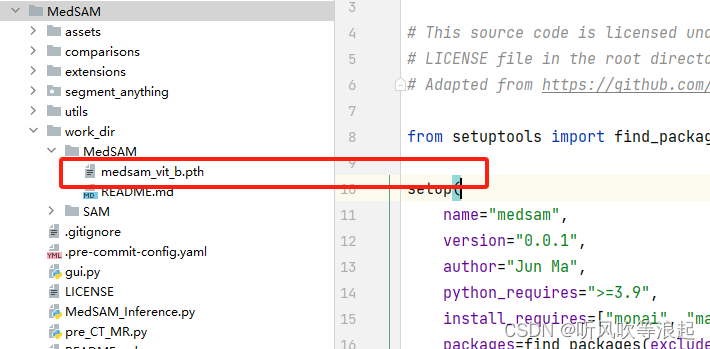

官方权重在这里:MedSAM - Google 云端硬盘

存放位置:work_dir/MedSAM/medsam_vit_b